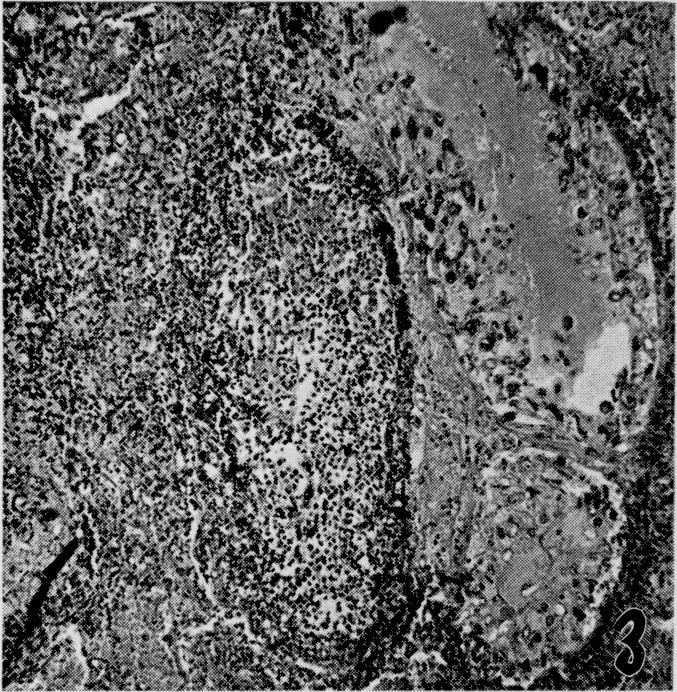

The effects of metabolic alterations on experimental Rhizopus oryzae (mucormycosis) infection.

Yale J Biol Med. 1956 Sep;29(1):23-32.